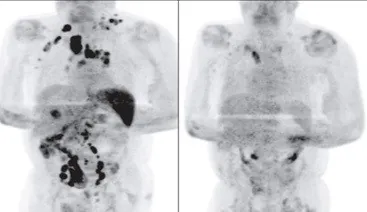

A 61‐year‐old man with stage III Hodgkin lymphoma was hospitalized for the infection of Covid-19 in the UK. He was hospitalized for 11 days and did not receive any cancer treatment. Four months later, the PET-CT scan result showed that his lymphoma was largely gone!

Left: Before, Right: After

Everyone were suppressed, including his doctors and the scientists who saw the results, and no one knows what has caused the cancer remission if no anticancer drugs have been given during the course of his disease.